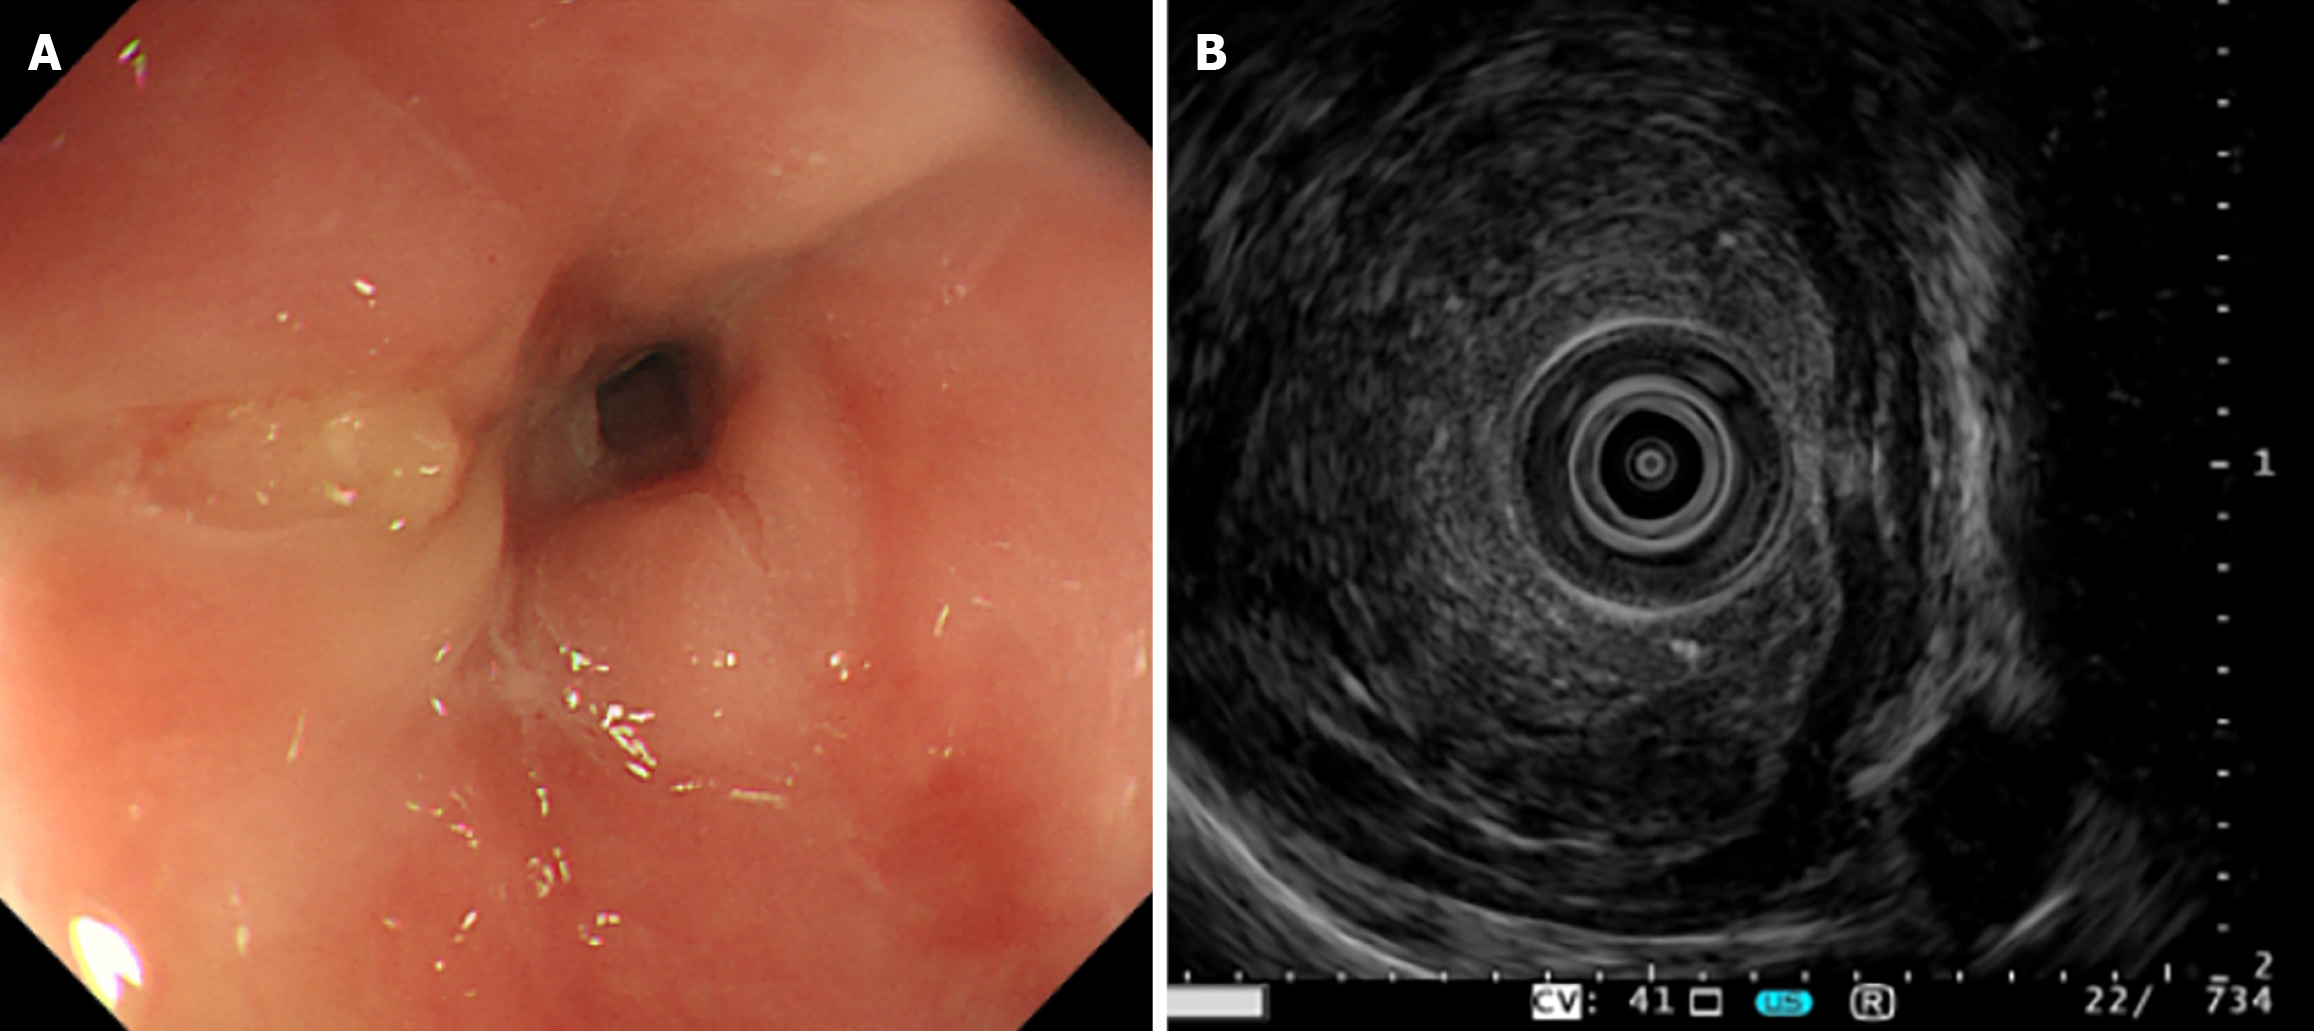

Figure 1 The endoscopic examination results indicated esophageal neoplastic lesions.

A: White-light endoscopy showing significant mucosal stenosis at 30 cm from incisors, with a soft and friable lesion; B: Endoscopic ultrasound demonstrating loss of normal mural layer structure and serosal interruption at lesion site (max wall thickness: 1.11 cm).